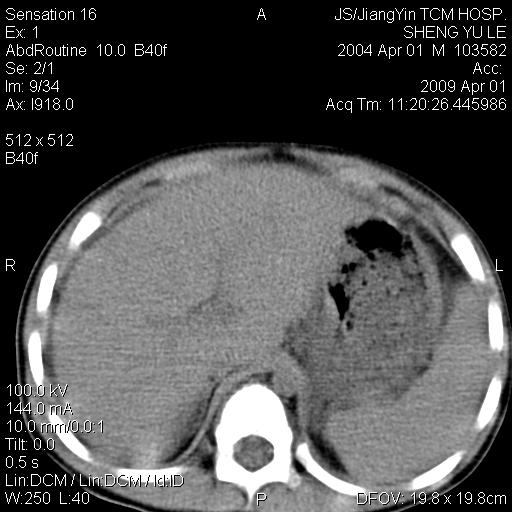

m,5岁。尿痛尿频数天。既往无病史。ct平扫腹盆腔积液。膀胱壁明显增厚。另可见心包增厚。wbc5万,骨髓穿等结果。请指教。

膀胱影像表现结合临床应该是急性膀胱炎症,但为什么有腹水呢?双肾输尿管无扩张,泌尿系压力应该不大不至于引起尿外渗,应该是腹膜感染引起的,但楼主没有提及相关症状,腹膜及膀胱结核?患者白细胞5万(结核不至于这么高啊),脾脏增大,是不是有白血病?进一步检查。。